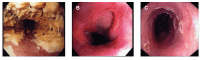

Figure 2.

Endoscopic views of severe Candida esophagitis (A), Cytomegalovirus ulcer (B), and herpes-simplex viral esophagitis (C).